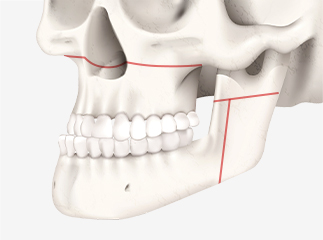

상악과 하악을 절골합니다.

절골된 상악과 하악을

수술 계획에 맞게 이동하여

교합을 맞춥니다.